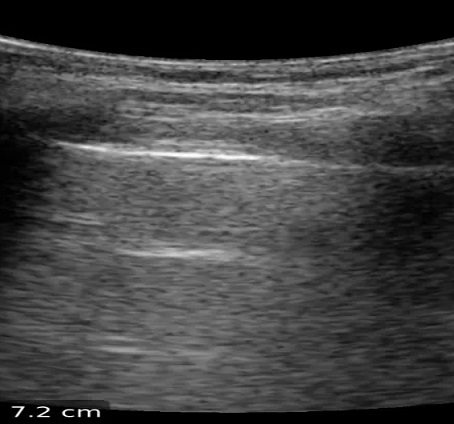

Aspect echographique normale

du poumon avec image en bande hyperechoic de la

plevre parietale et viscerale .Normalement sur le

coupe à sonde convex 3,5MHz on peut en vue plusieur

de ligne de reflexion A ( fleche blanche ) , aspect

de glissement pleurale et sur mode T-M image

echographique se presence de aspect de bord de mere

" seashore sign " et les deux plevres apparait en

bande hyperehogene |

Normalement la reflexion de

onde de echo sur deux tissu à difference de

caractere : le tissue mou de la paroi et tissue à

plein air de la parenchyme pulmonaire se donne de

image de " "queue du comet " |